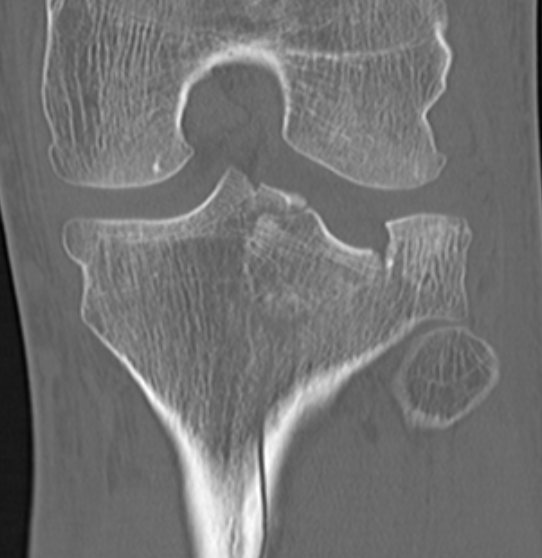

IV. Medial plateau & intercondylar eminence

- high velocity injury associated with ACL / LCL / CPN injury

- can be low injury / osteoporotic and often unreconstructable